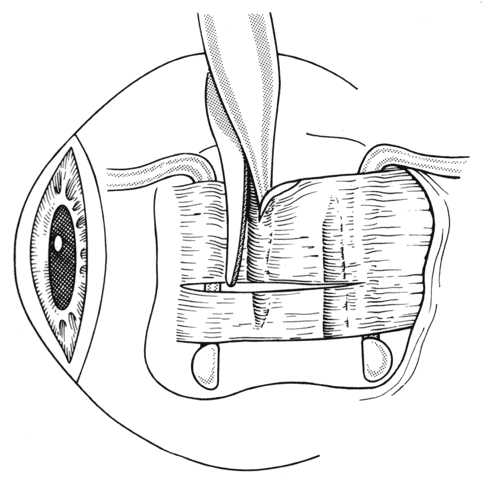

If a muscle tendon has been split during mobilization of the tendon or by passing a muscle hook under a scarred tendon, the marginal myotomy should be avoided. Placing cuts in the muscle may cause the muscle to be transsected (Figs. 37 through 40).

Fig. 37. When a muscle is split, a marginal myotomy is contraindicated.

Fig. 38. The split muscle is clamped.

Fig. 39. The cuts in the muscle divide it.

Fig. 40. The muscle can retract into the orbit.